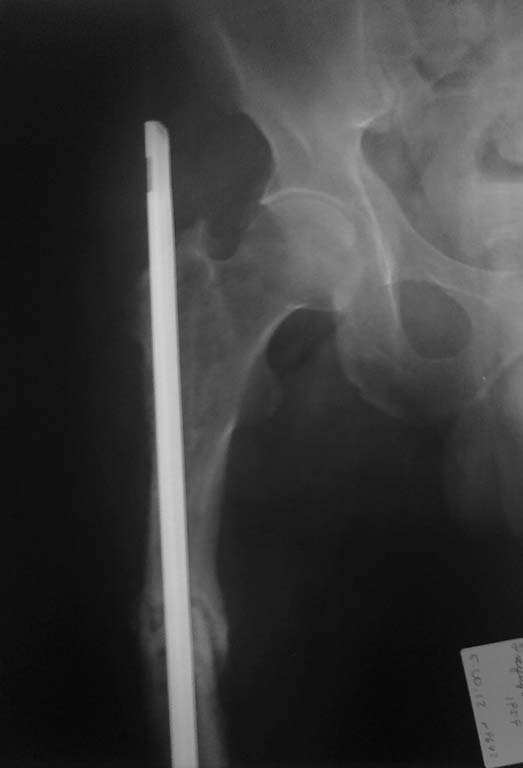

Только по поводу перелома бедренной кости 2-операция. 1.открытая репозиция экстрамедуллярный металлоостеосинтез. Через 6-7 мес перелом импланта. 2. удаление пластины и интрамедуллярный металлоостеосинтез гвоздем Кюнчера (2010г). В данный момент разгибательная контрактура коленного сустава, укорочение правой н/к на 4-5 см, боли в области правого тазобедренного сустава и бедра. Потологической подвижности не определяется, передвигается с помощью костылей.

На рентгенограмме признаки консолидации слабо визуализируются, дистальный конец стержня перфорировал метаэпифиз бедренной кости (в коленном суставе), проксимальный конец бедренной кости так же разрушен. Планируем варианты удаление стержня, рассверливания КМК, БИОС анатомическим бедренным стержнем + удаление металлоконструкций из других костей. У кого какое мнение и тактика в данном случае. Заранее всем спасибо. P.S: удлинение сегмента пациент не хочет (-устал от операции)